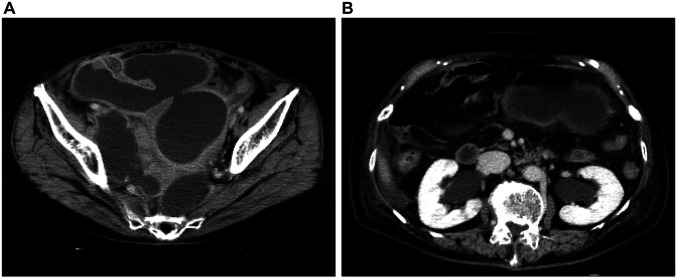

Case report: A 78-year-old woman underwent robotic-assisted abdominoperineal resection with right LLND for lower rectal cancer. She was discharged on postoperative day 12 but developed right lower abdominal pain on day 7 after discharge. Computed tomography revealed a fluid collection in the LLND area, diagnosed as a lymph cyst. Despite computed tomography-guided percutaneous drainage, the output remained high, and symptoms persisted. On hospital day 18, lymphangiography was performed using Lipiodol via right inguinal lymph node puncture. Within 3 days, the drainage output significantly decreased, and her symptoms improved.